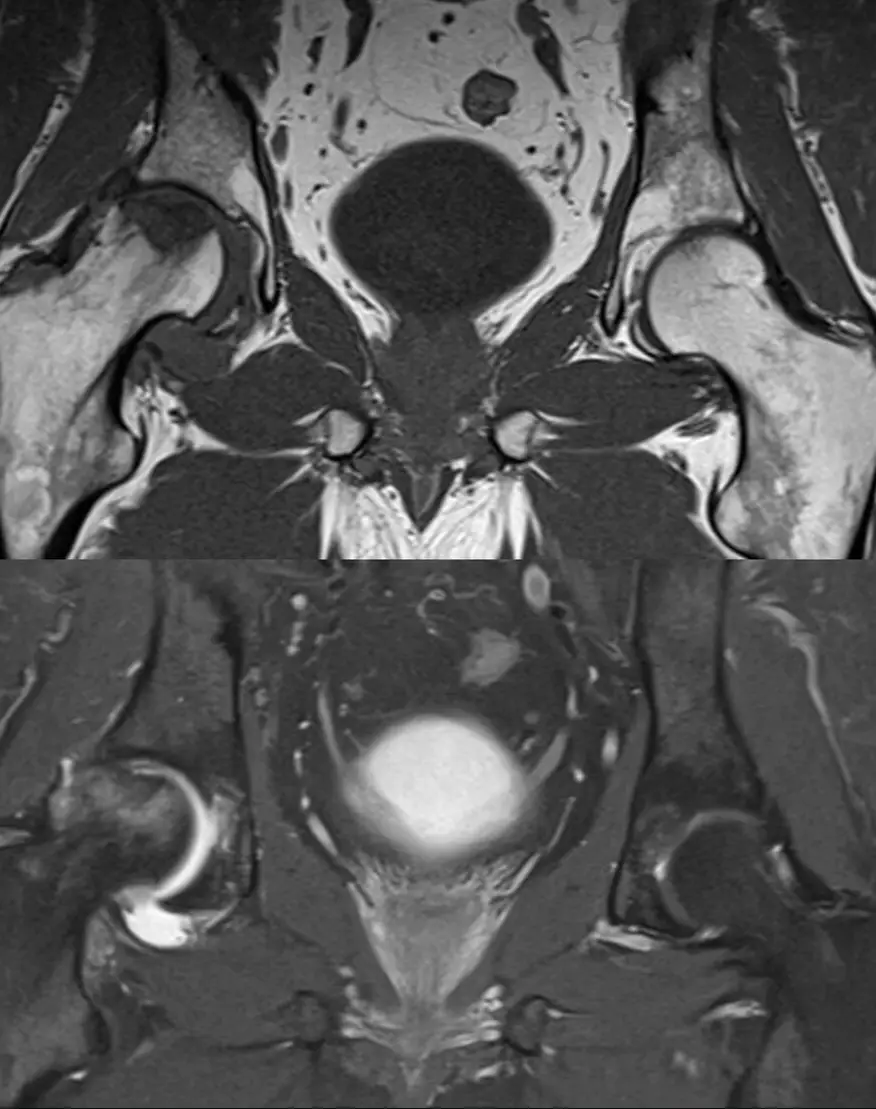

МРТ тазобедренного сустава (пара)

Визуализация костей тазобедренного сустава, суставная губа, суставная капсула, параартикулярные ткани.